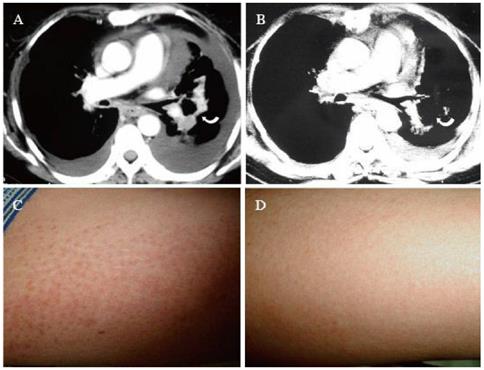

皮肌炎

一些非小细胞肺癌尤其是肺腺癌的患者,可能在诊断前平均约2年内的时间里,在脸部、颈部、上胸、背部、双侧肘部、双手背侧的关节等部位出现对称性皮疹,皮疹的颜色大多为暗红色,一些病情进展迅速的偶尔也可呈猩红色,这些皮疹在给予外用激素类药物治疗后可以短暂褪去,但很快又会再次出现,出现皮疹的同时有时会伴有肌肉的酸痛。上述现象在临床上被称为“皮肌炎”,这是一种已被证实与内在恶性肿瘤密切相关的体表现象。

一患者的皮肌炎表现在肺癌得到控制后完全消除